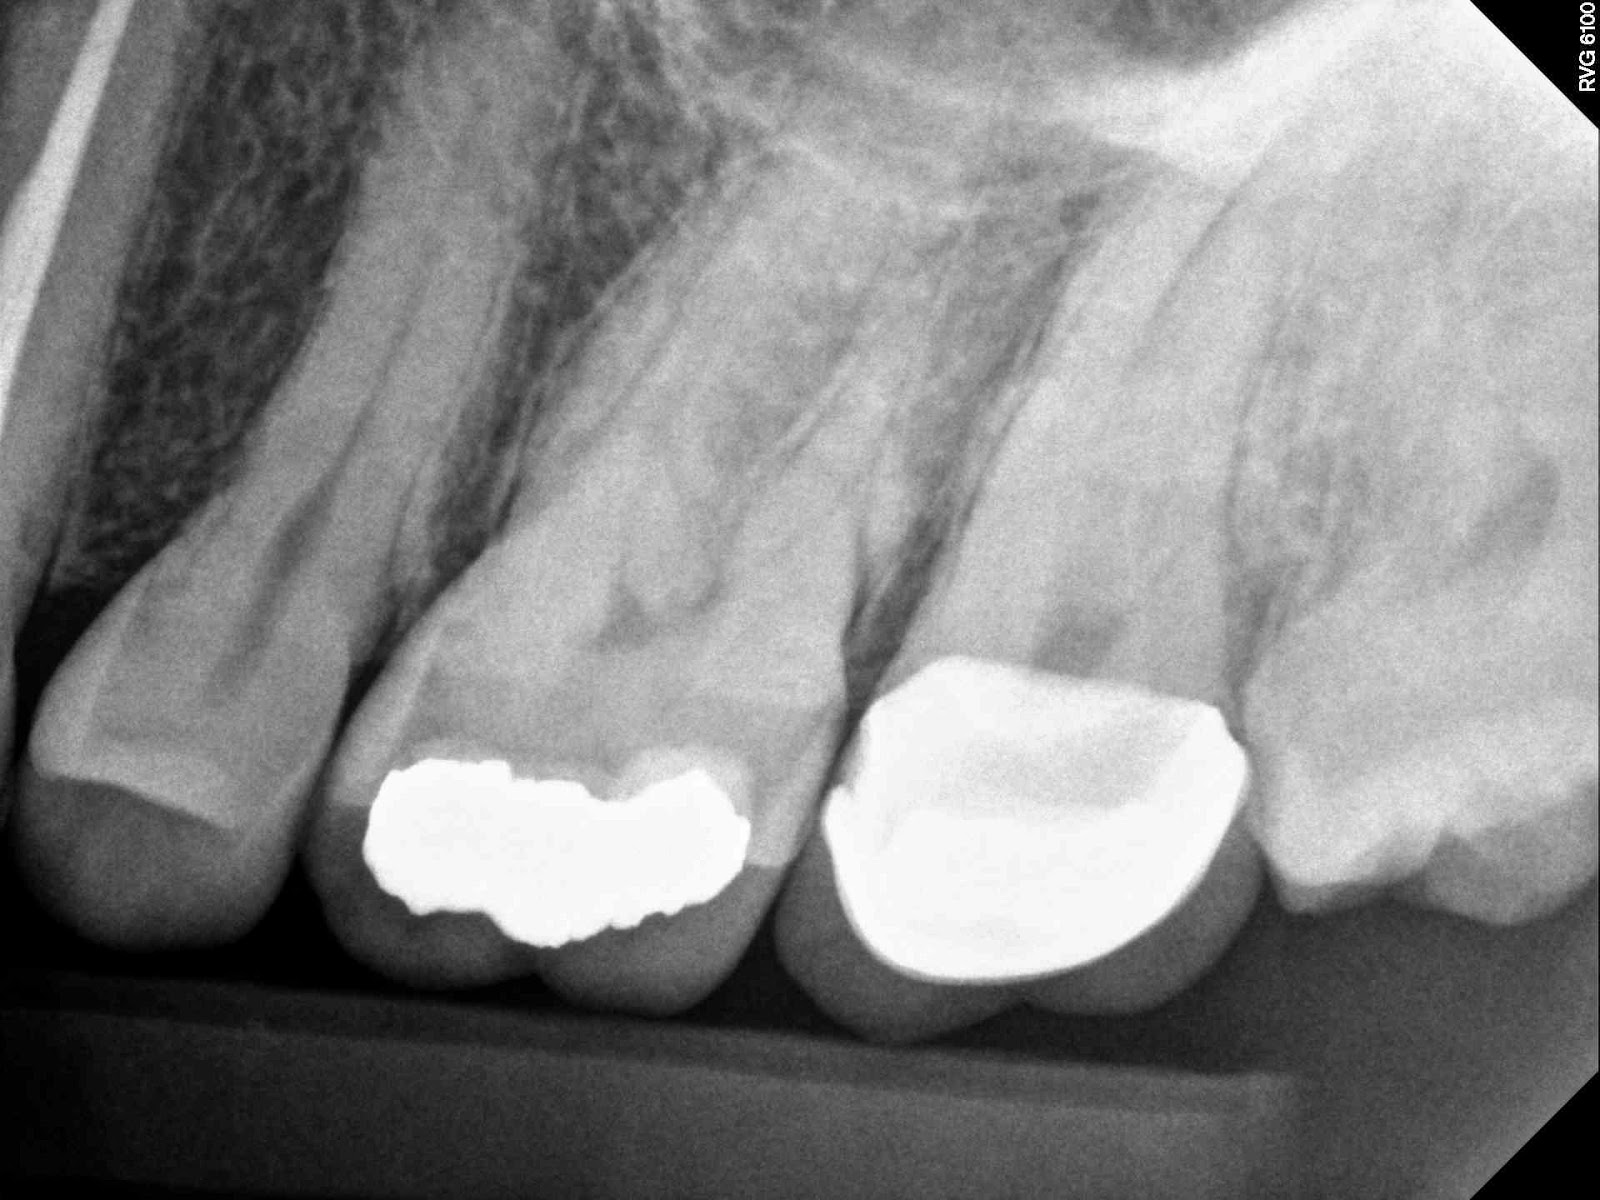

Tooth vital – tooth necrotic

# teeth with MB2 present- able to cleanse and shape the MB2 – MB2 join

MB1 – teeth I consider calcified that no MB2 was found – total # of 1st

molar treated

MB2 distance from MB1 – join MB1

12-11=23

19-16-8-0-23

this was more of a fin than a true second canal-yes